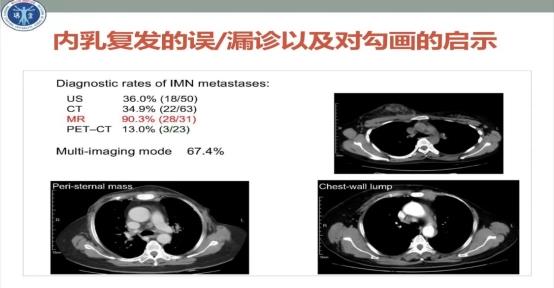

内乳复发的误/漏诊以及对勾画的启示